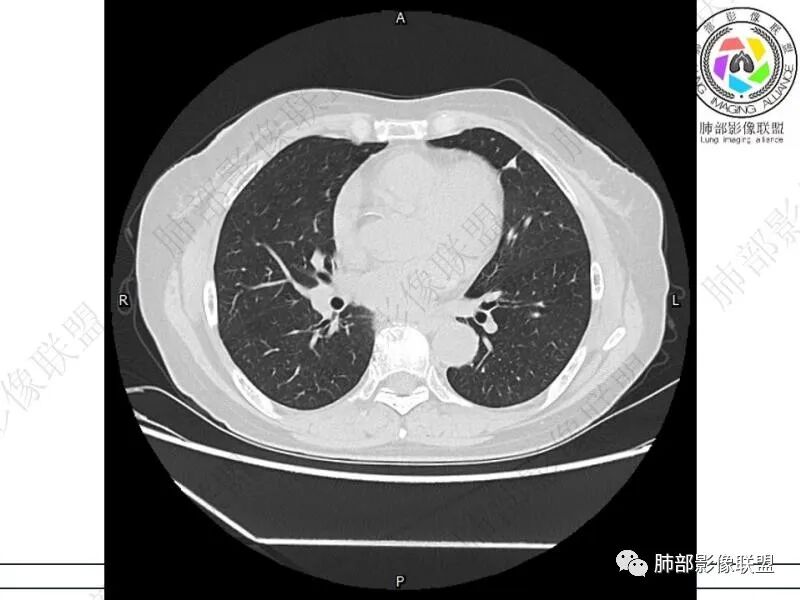

摘星空竹子:两肺胸膜下多发实性结节、磨玻璃影及实变影,短期复查病变有所进展,考虑感染性病变,隐球菌可能,患者有右半结肠癌手术史,转移不能除外。

简单:双肺及胸膜下多发小结节,双下肺胸膜下宽基底团块影,短期内病灶进展考虑炎性病变,隐球?患者ca术后,双肺小结节随诊除外转移

丽:双肺下叶胸膜下多发片状高密度影,边缘模糊不清,内可见支气管穿行,病变长轴平行于胸膜,考虑感染性病变,隐球菌

媛:肠癌术后,免疫力低下。两肺胸膜下结节及实变影,实变影长轴平行于胸膜,密度均匀,边界偏清,周围有晕征,短期复查进展,虽隐球菌荚膜抗原检测阴性,还是考虑隐球菌,鉴别OP

谢加平:结肠癌术后史,两肺胸膜下多发结节及斑块实变病灶,实边边界平直征(亚急性和慢性病变过程),双肺下叶后基底段胸膜下为甚,与胸膜平行特点,见支气管充气征,边缘模糊的GG0,首诊2022年11月18日肺部CT,与治疗11月28日对比,病灶未吸收,双肺下叶胸膜下病灶有侧向融合特点,综合分析符合炎性肉芽肿,隐球菌感染。

老年女性,结肠癌术后。两下肺胸膜下为主片状实变,右下肺短期复查融合且病灶长轴平行于胸膜,实变内可见支气管充气征,边缘磨玻璃晕,另两肺内胸膜下散在数枚小结节状、楔形实性灶。考虑感染性病变,隐球菌可能,鉴别肺转移。

2.影像特征:双肺胸膜下多发实性结节、磨玻璃影及实变影,胸膜下优势分布、晕征、胸膜下脂肪间隙存在,部分病灶边界平直征,有侧向融合趋势。